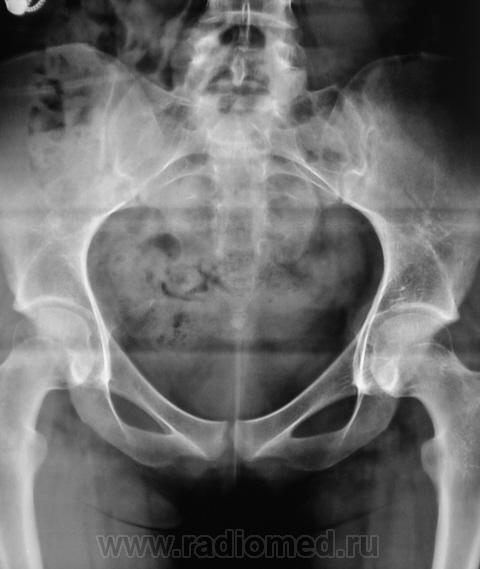

Из анамнеза известно, что примерно 2 месяца тому "летела" со сноутборга около 200 метров. Сейчас беспокоят боли в области спины, крестца и лонного сочленения. УЗИ было сделано всего, что только можно, везде - "норма". Хирурги, вроде-бы тоже ничего не находят. Но боли, видать значительные, походка вынужденная. На рентгенографию была направлена, как жест отчаяния, мол может быть, что-то найдут.

Так как "содержимое кишечника" не способствовало анализу изображений, пациентке было предложено, посетить кабинет повторно.

Рентгенограмма в прямой проекции.

1. Не исключаю поперечный перелом S5.

2. Лонное сочленение очевидно,подверглось значительному растяжению (имеется локальный вакуум-феномен слева), умеренно выраженые явления симфизита (опять же - постравматического).

Посттравматический симфизит - это такой медицинский диагноз есть? Тогда уж лучше - симфизопатияУлыбаюсь.  По поперечному перелому Л5 - тангенциальный эффект, сложение теней. По хорошему, надо бы доснять поясничный отдел позвоночника, в том числе в косых проекциях - на дугоотростчатые суставы, и грудо-поясничный переход.

1. По первым снимкам не отпускало впечатление о повреждении левого крестцово-подвздошного сочленения. После подготовки вроде-бы все нормально, но все равно что-то гложет.

Верятность перелома остистого отростка Л4 очень велика. Это находит подтвеждение и на боковом снимке.

Поздно заметил ветку.. увидел симфизит, перелом остистого L4, мазоль Co 5, и  конечно spina bifida S1 ))) глянуть бы межпозвоночные..